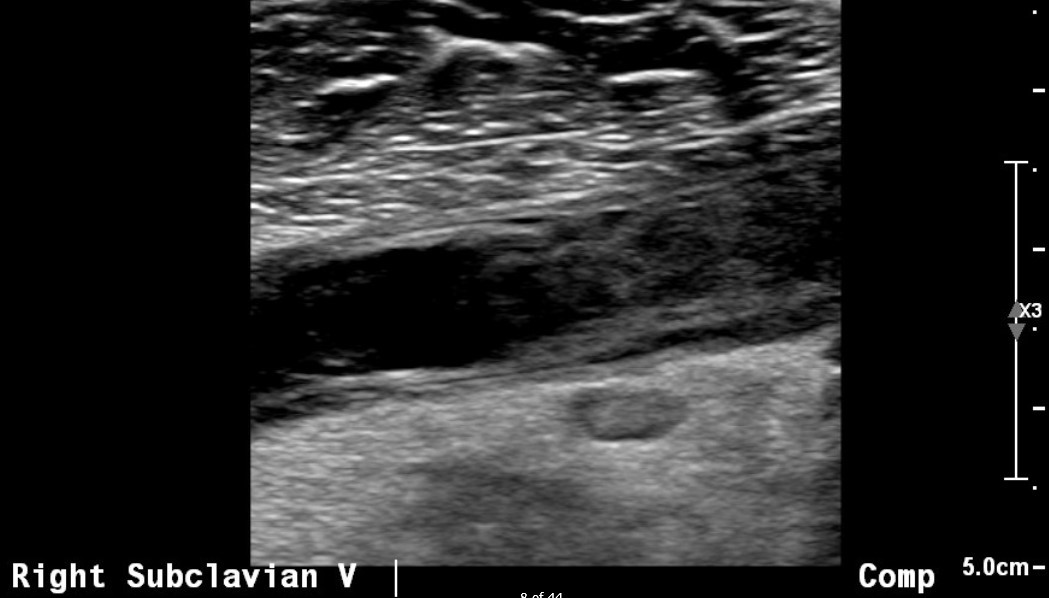

When a patient presents with an acute clot, imaging is usually done with duplex ultrasound. It is a highly sensitive test in experienced hands. Acutely, you will find a subclavian vein thrombus that will often extend to the axillary vein: